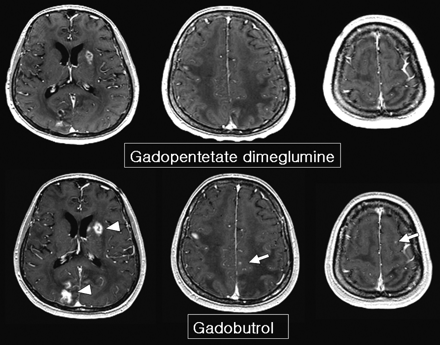

On the DD gadopentetate dimeglumine−enhanced images, a total of 130 lesions were detected. Among 27 patients, 13 patients had a solitary lesion, 3 had 2 lesions, another 2 had 3 lesions, and 9 had multiple lesions. With DD gadobutrol, 25 additional lesions were detected on localization MR imaging for GKS in 7 patients (Fig 1). All 25 lesions were not evident on DD gadopentetate dimeglumine images. Of the 25 lesions, 1 patient had a solitary lesion, 3 had 2 lesions, 2 had 3 lesions, and 1 had 12 lesions.

The lesion-brain CNR was higher on DD gadobutrol MR imaging (2.17 ± 0.19 versus 1.90 ± 0.26; P = .00011, paired t test, 2-tailed) (Fig 1). Gadobutrol MR images showed thicker enhancing rims of metastatic masses (Fig 2) and better lesion contrast than gadopentetate dimeglumine images (Fig 3). Only 2 cases had lower CNR on DD gadobutrol images: 1 had hemorrhagic metastasis from renal cell carcinoma and another started steroid treatment after the first MR imaging. The CNR was 1.78 on gadobutrol MR imaging and 2.25 on gadopentetate dimeglumine MR imaging in the first patient. In the second patient, the CNR was 2.29 on gadobutrol MR imaging and 2.73 on gadopentetate dimeglumine MR imaging.

A 63-year-old woman with lung cancer. Gadobutrol MR imaging shows more enhancing lesions than gadopentetate dimeglumine MR imaging (arrow in the right precentral gyrus). Retrospective review of gadopentetate dimeglumine images suggests the existence of a small nodule in the right precentral gyrus, but it is not definite. A thicker enhancing rim and prominent gadolinium spillage are seen on gadobutrol MR imaging (arrowheads).

A 60-year-old man with lung cancer. Gadobutrol MR imaging shows more enhancing lesions than gadopentetate dimeglumine MR imaging (arrows). There is no suspected lesion on gadopentetate dimegluimine MR imaging. Note the higher signal intensity of the thick enhancing rim (arrowheads). The interval between the 2 MR images is 60 hours.